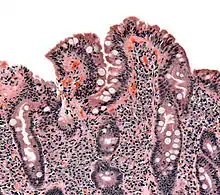

Gastrointestinal Physiology looks at the functioning of the Gastro-Intestinal (GI) system. The four basic functions of the GI system are digestion, absorption, motility and secretion. Digestion describes how ingested food is broken down into smaller biochemical components; absorption how the products of digestion are absorbed into the body; motility how food and waste products are moved from mouth to anus; and secretion how digestive juices etc. are controlled and secreted. About 9 liters of fluid pass through the GI system every day, and of these only two are taken by mouth, the rest represents secretions by the system itself.

The digestive system is the body's major interface with the out side world, and as such it is richly supplied with immune cells, indeed by some estimates 80% of the bodies immune cells are in the GI tract.